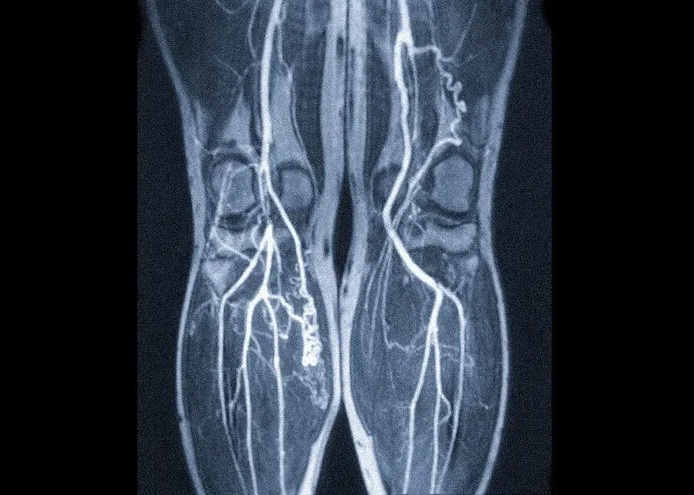

По результатам МР-ангиографии сосудов нижних конечностей получаются черно-белые изображения с очертаниями ног, внутри которых расположены подсвеченные артерии, вены и менее крупные их ответвления. На сканерах высокого разрешения можно различить даже микроскопические капилляры. Кости и соседние мягкие ткани отходят на второй план, ветви кровеносной сети становятся более светлыми и контрастными, что позволяет изучить их строение и найти патологии.

Низкомощная аппаратура с показателями магнитного поля менее 1 Тесла не подойдет. В этом виде исследования требуется максимальная детализация, которая доступна на высокопольных аппаратах с минимальными показателями 1,5 Тесла. Лучших результатов достигают на установках от 3 Тесла и выше, их разрешение позволяет увидеть не только строение кровеносной сети, но и структуру отдельных участков сосудистой стенки.